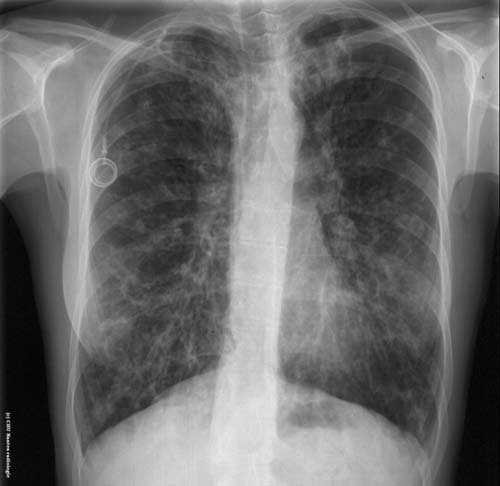

Dilatations des bronches (

DDB

)